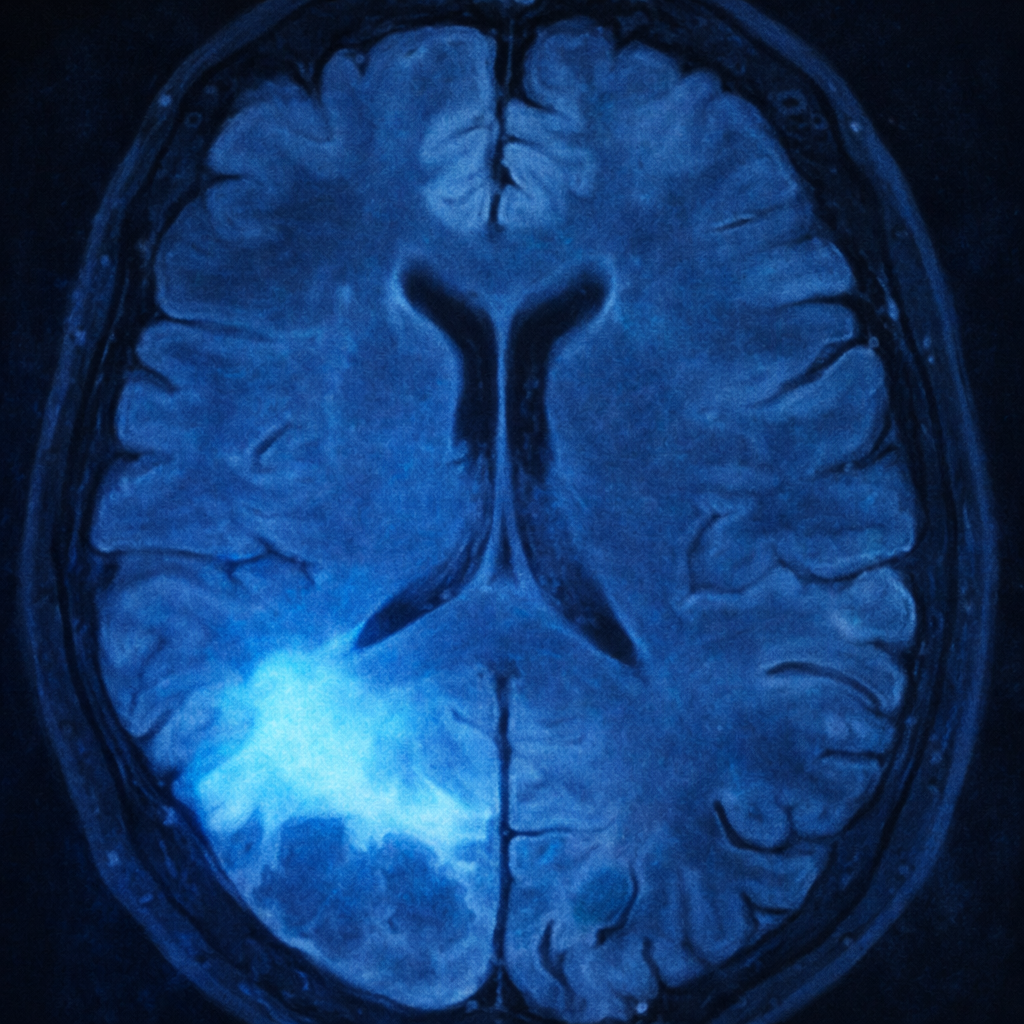

Las metástasis cerebrales pueden presentarse como lesiones únicas o múltiples. Se caracterizan por la captación de medio de contraste en forma de anillo y por la presencia de mucho edema alrededor del tumor.

El estudio inicial para identificar metástasis cerebrales es la resonancia magnética cerebral con gadolinio o medio de contraste. En este estudio, es característico encontrar una o más lesiones cerebrales que captan medio de contraste y que presentan un muy importante edema o inflamación perilesional.